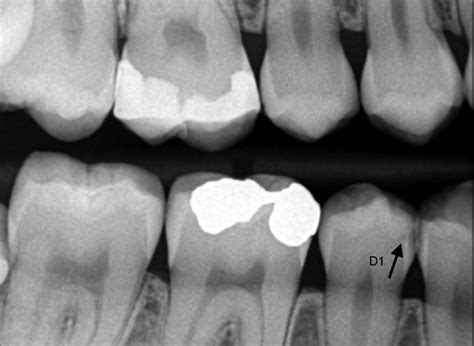

La desmineralización y destrucción de las capas del diente se observa como una imagen radiolúcida (zona negra alrededor/dentro del diente).

En la imagen que señala la flecha vemos una imagen radiolúcida (oscura) que indica la falta de material dental, la presencia de una zona “hueca”. Caries.